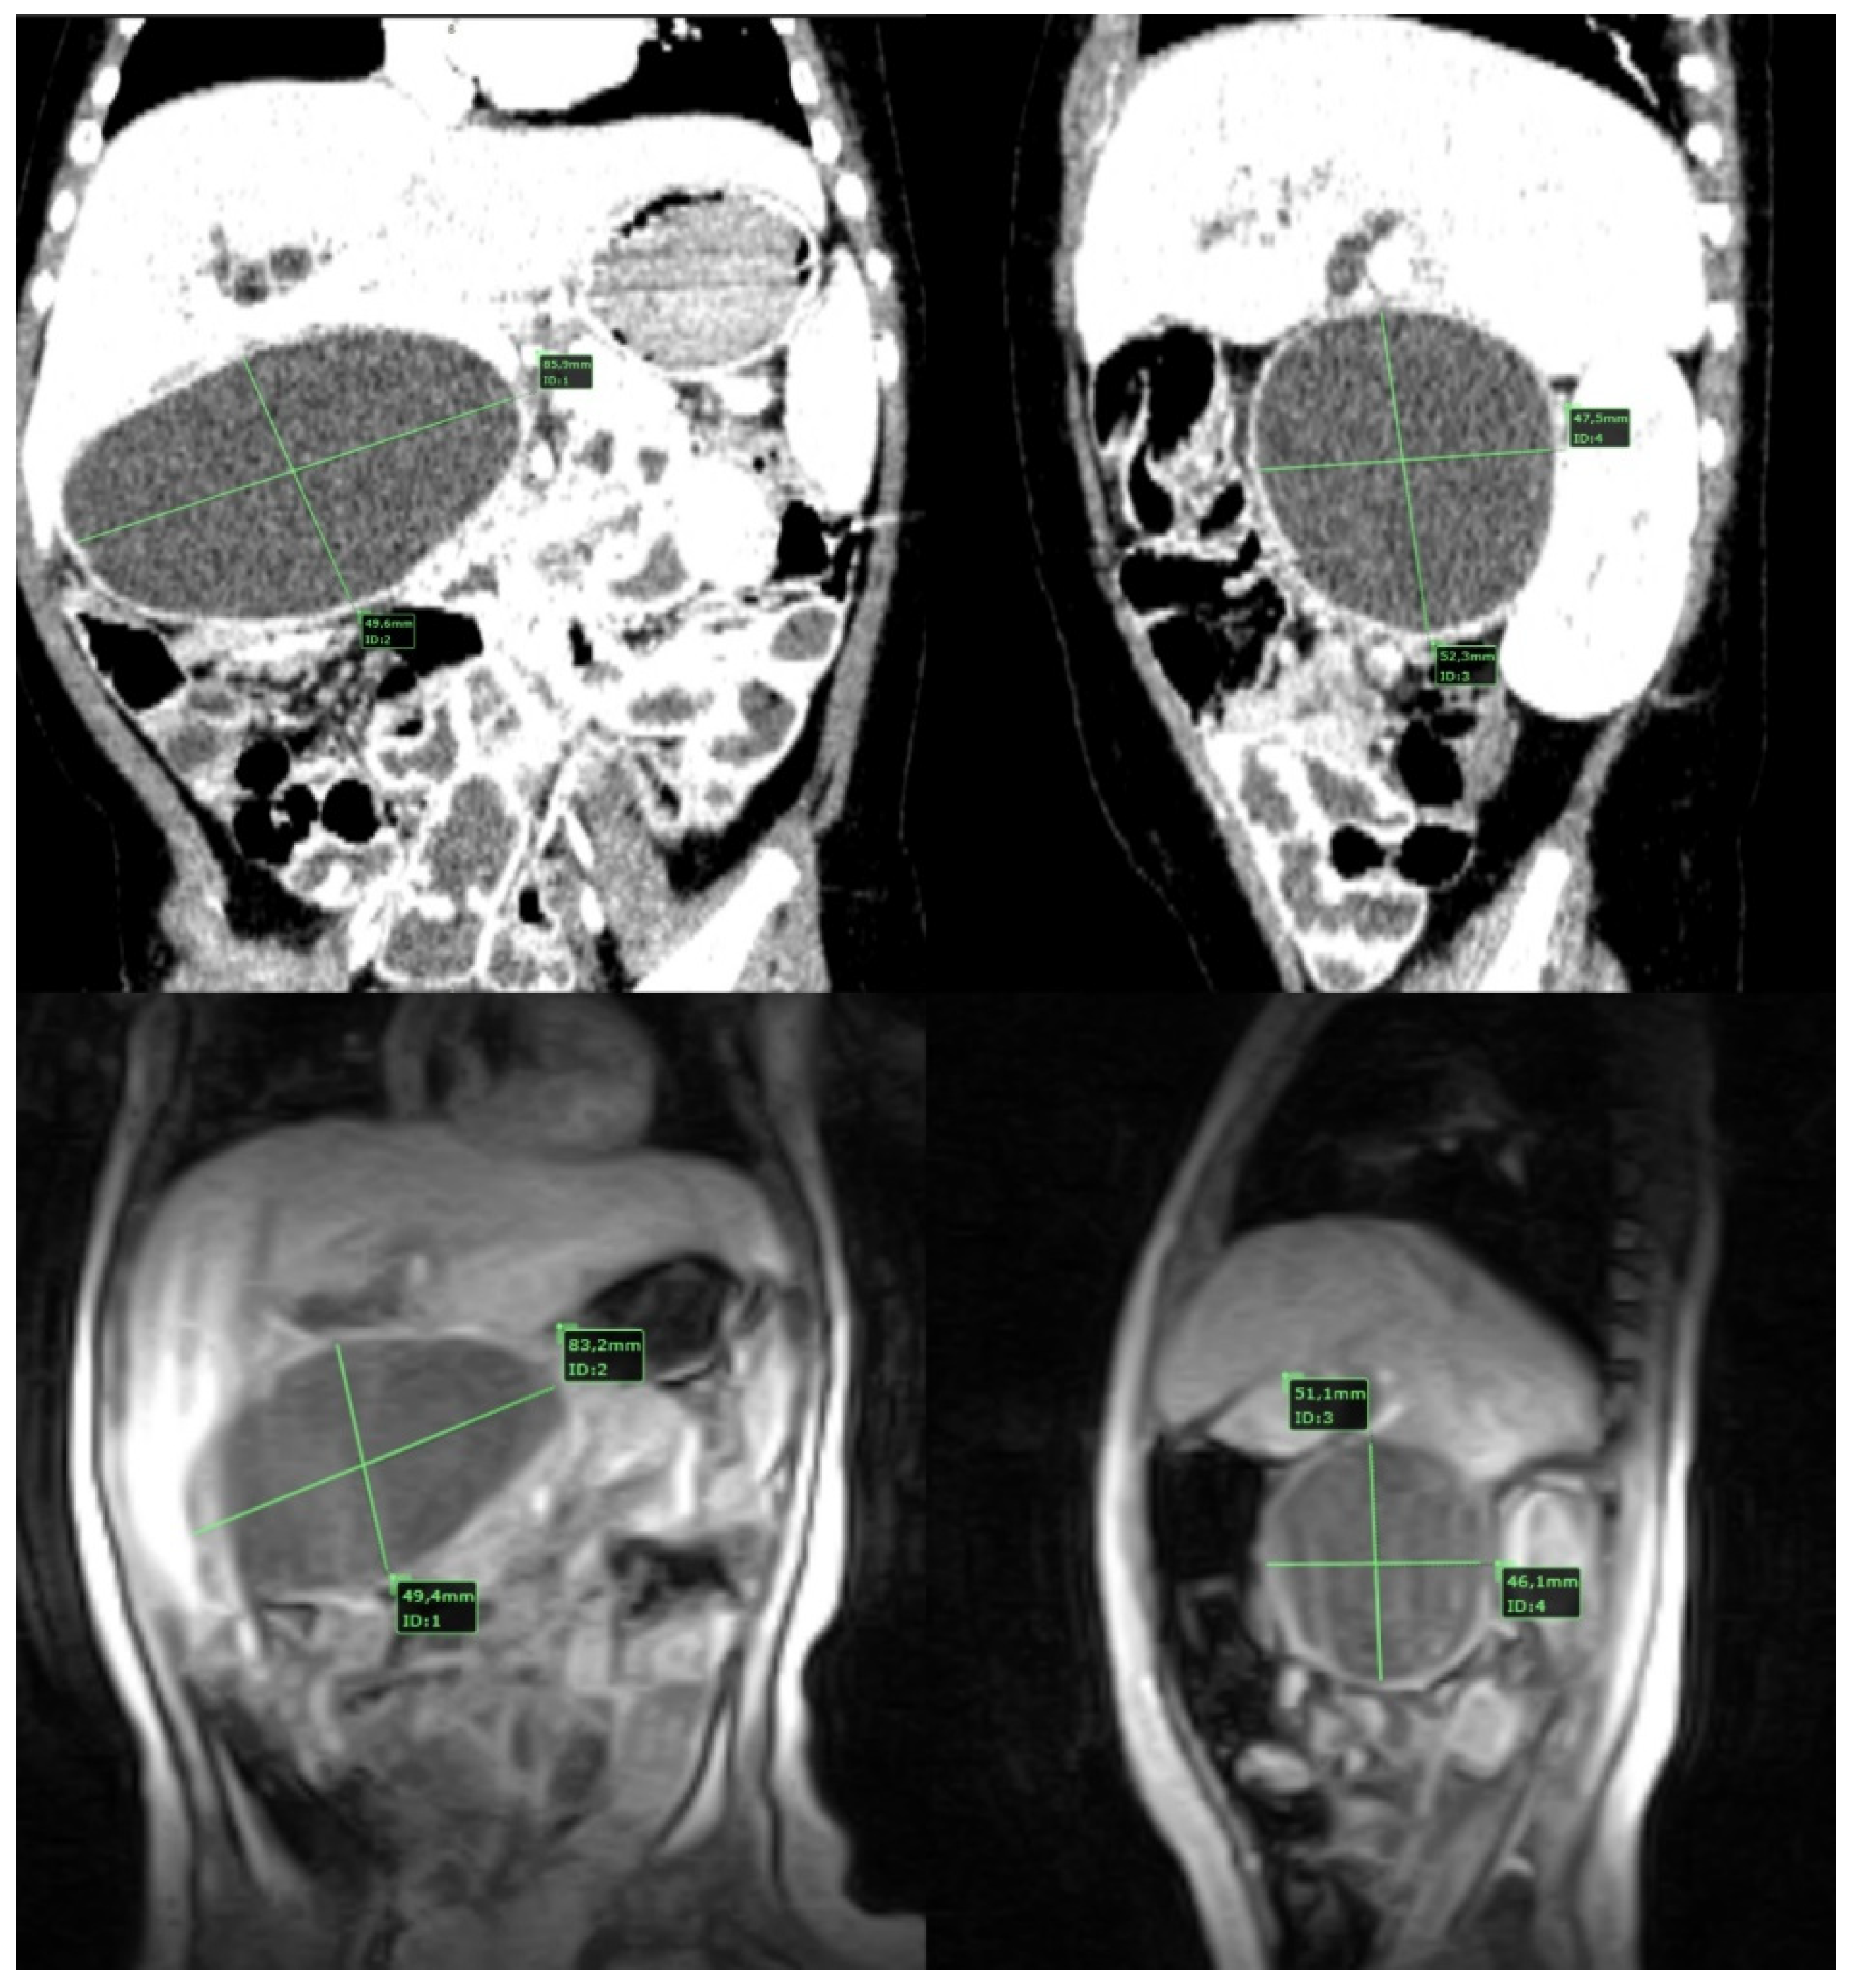

| Ns | Jd | AP | AM | As/Hu | Pt | Cl | US | CT | MRI | Cyst Type | Cyst Dimension (mm) * | Liver Disease | |||||||

| 1 | 63 | F | Yes | Yes | No | No | No | No | Yes | Yes | No | No | HD | Open | No | 1C | 90 | N | 28 |

| 2 | 26 | F | Yes | No | No | No | No | No | No | Yes | No | No | HD | Lap | No | 1C | 25 | N | 12 |

| 3 | 204 | F | Yes | No | No | No | No | No | No | Yes | No | Yes | HD | Lap | No | 1B | 39 | N | LTF |

| 4 | 36 | F | Yes | Yes | Yes | No | No | Yes | Yes | Yes | Yes | No | HJ | Open | Yes—Pt | 1C | 54 | N | 6 |

| 5 | 23 | F | No | Yes | Yes | No | No | No | Yes | Yes | Yes | No | HD | Lap | No | 4A | 26 | CH | 12 |

| 6 | 120 | M | Yes | No | Yes | No | No | No | No | Yes | Yes | No | HD | Lap | No | 1B | 30 | N | 48 |

| 7 | 35 | M | Yes | Yes | Yes | No | No | No | Yes | Yes | Yes | No | HD | Lap | No | 1A | 42 | N | 16 |

| 8 | 18 | M | No | Yes | No | No | Yes | No | No | Yes | Yes | No | HJ | Open | No | 1C | 48 | N | 10 |

| 9 | 14 | F | No | No | Yes | No | No | No | No | yes | Yes | Yes | HJ | Open | No | 4A | 14 | N | 24 |

| 10 | 2 | M | Yes | No | No | No | No | No | No | Yes | Yes | No | HD | Open | No | 1C | 30 | N | 36 |

| 11 | 82 | F | Yes | Yes | Yes | Yes | No | Yes | Yes | Yes | Yes | Yes | HD | Lap | Yes—AL | 1C | 99 | N | LTF |

| 12 | 84 | F | Yes | Yes | Yes | Yes | No | No | Yes | Yes | Yes | Yes | HJ | Open | No | 1C | 60 | N | 12 |

| 13 | 4 | M | No | Yes | No | No | Yes | No | No | Yes | Yes | No | HJ | Conversion | No | 1C | 23 | VH | Deceased |

| 14 | 2 | F | No | Yes | No | No | No | Yes | No | Yes | Yes | No | HJ | Open | No | 1C | 40 | N | 3 |

| 15 | 84 | M | Yes | Yes | Yes | No | No | No | No | Yes | No | No | HJ | Open | No | 1C | 60 | N | LTF |

| 16 | 54 | F | No | No | Yes | No | No | No | Yes | Yes | Yes | No | HJ | Open | No | 1A | 80 | N | 3 |